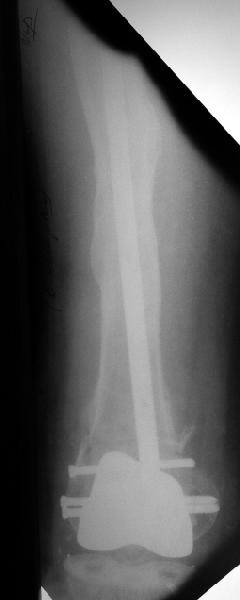

В итоге сделали антеградный остеосинтез. В дистракторе свежий перелом вправился сразу, а вот старый - оставил проблему, дистальный отлмомк остался все равно кзади. И гвоздь бы прошел кпереди от него, а ретроградный - перфорировал бы передний кортекс. Так что пришлось еще сделать чрескожную остеотомию через перелом, чтобы малость мобилизовать дистальный отломок. Снимки в прилжении.